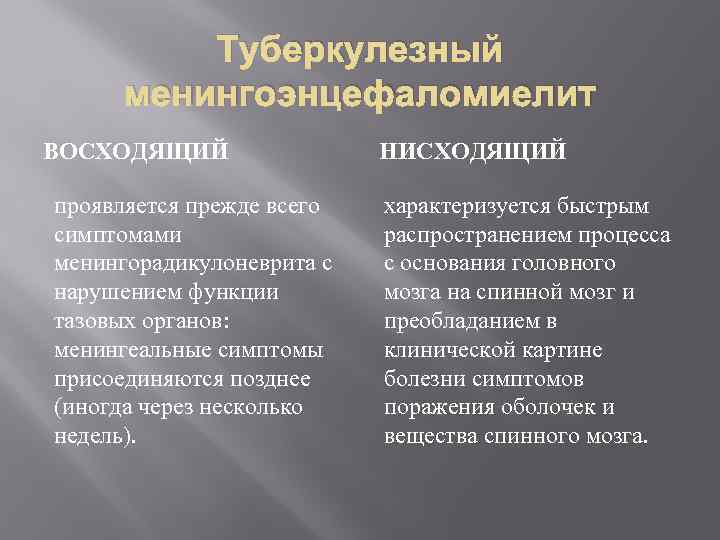

Туберкулезный менингоэнцефаломиелит ВОСХОДЯЩИЙ проявляется прежде всего симптомами менингорадикулоневрита с нарушением функции тазовых органов: менингеальные симптомы присоединяются позднее (иногда через несколько недель). НИСХОДЯЩИЙ характеризуется быстрым распространением процесса с основания головного мозга на спинной мозг и преобладанием в клинической картине болезни симптомов поражения оболочек и вещества спинного мозга.

Туберкулезный менингоэнцефаломиелит ВОСХОДЯЩИЙ проявляется прежде всего симптомами менингорадикулоневрита с нарушением функции тазовых органов: менингеальные симптомы присоединяются позднее (иногда через несколько недель). НИСХОДЯЩИЙ характеризуется быстрым распространением процесса с основания головного мозга на спинной мозг и преобладанием в клинической картине болезни симптомов поражения оболочек и вещества спинного мозга.